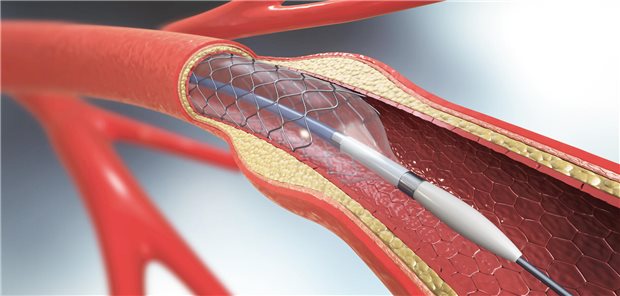

Lipidsenkung

LDL-Cholesterin: PCSK9-Inhibitor Evolocumab reduziert Risiko für erstes kardiovaskuläres Ereignis